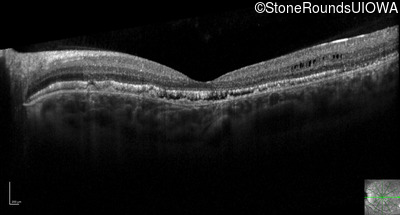

Optical Coherence Tomography - Right - 20/100 sc

Exemplar / OCT Stack